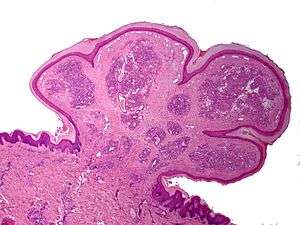

One study has suggested a correlation between pyogenic granuloma and Bartonella seropositivity.[7] However, this association has been questioned by others.[8] The appearance of a pyogenic granulomas microscopically has a highly vascular granulation tissue. Inflammation is present. The lesion may have a fibrous character if it is older, and the surface may have ulcerations. Pyogenic granuloma rarely occurs in the conjunctiva, cornea or connective tissue of the eye following minor local trauma. Grossly these mass lesions resemble those occurring at more common sites. The relationship of this lesion to the lobular capillary hemangioma of skin and oropharyngeal mucosa commonly referred to as pyogenic granuloma is uncertain.